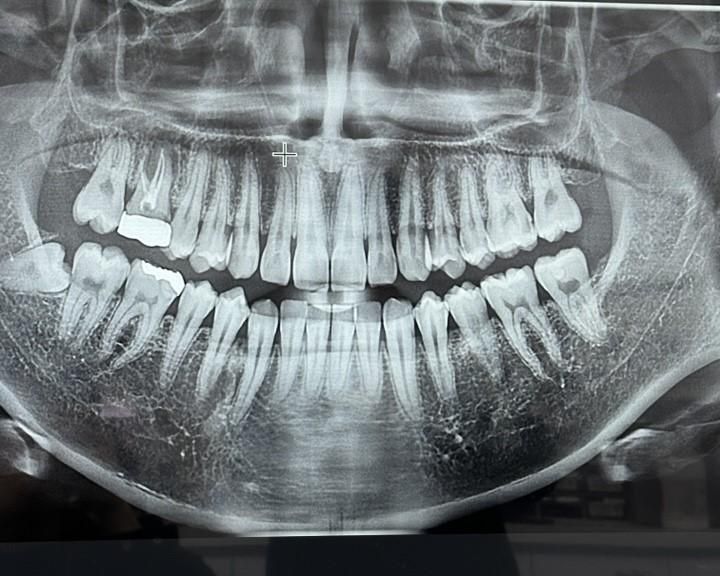

• 1번 째 사진

현재 임플란트 급해서 임플란트 하고있는 치과 인데요, 발치 하고 플리퍼 본 까지 떴는데, 그 외 나머지 충치 들?? 치료까지 진행하려고 하였습니다. 근데 약간 인레이와 크라운쪽으로 좀 몰아가는 보철? 식 치과인 거 같아서요. 열심히 찾아보면서 느낀 건. 인레이와 크라운이 최선인 경우도 있다곤 하지만, 제가 듣고, 보기엔+유튜브 열심히 찾아도 봤는데 보전식 치료가 암만 생각해도 맞는거 같아서 나머지 이빨들은 레진이나, 레진 (빌드업) 치료로 다 받고싶은데 가능한가요 ?

• 오른쪽 6은 어제 발치 하였습니다.